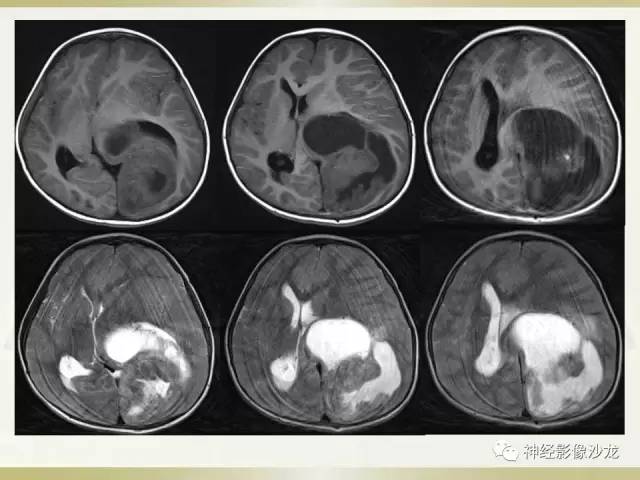

【病例】幕上脑实质内室管膜瘤1例CT及MR影像讨论

T1像有点状高信号

就对应钙化

T1WI点状高信号

侧脑室三角区受压

间变了室管膜瘤?

水肿轻度,